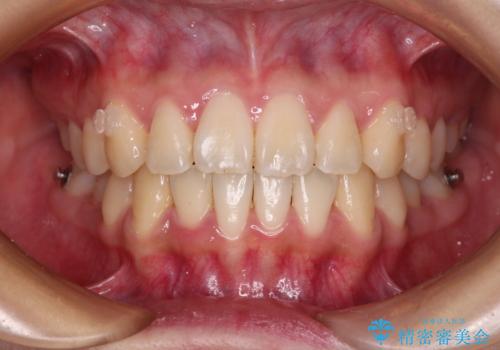

- 前歯の捻れを気にして来院された患者様です。

上顎前歯が捻れて前方に飛び出しており、下顎前歯もそれに沿うようにデコボコとなっていました。

IPR(歯と歯の間を削る処置)によりスペースを獲得して下顎前歯のデコボコを改善し、上顎前歯は下顎前歯と接する位置にまで引っ込めるように設定し、インビザラインにて矯正治療を行うこととしました。

しっかりと装着時間を守ってくださったので、予定通り1年強で治療を終えることができました。